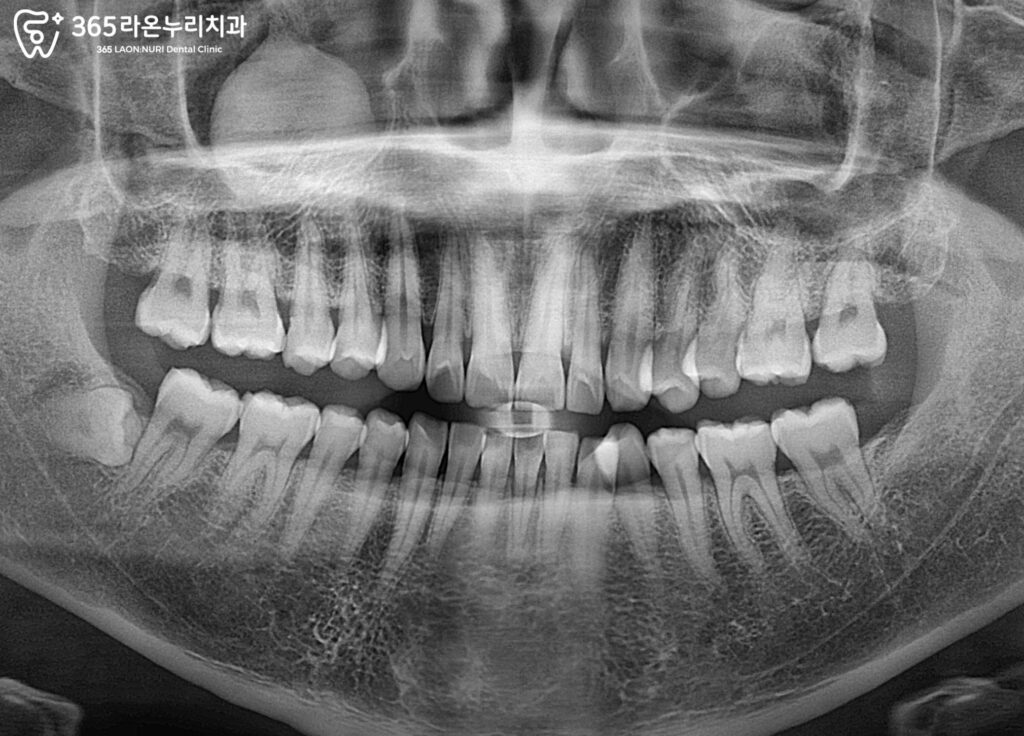

엑스레이를 통해 치아 내부 확인

구강 내에서 우식이 확인되면,

단순히 겉모습만으로는

치료 범위를 정확히 판단하기 어렵습니다.

따라서 엑스레이 촬영을 통해

병소가 치아 내부 어느 정도까지

진행되었는지를 먼저 확인합니다.

만약 우식이 작고 국소적이라면,

손상된 부분만 제거한 후

레진 수복으로 마무리할 수 있습니다.

신경까지 닿지는 않았으나

그 거리가 가까우며 범위가 다소 클 때는

인레이 수복을 통해 강도를 보강합니다.